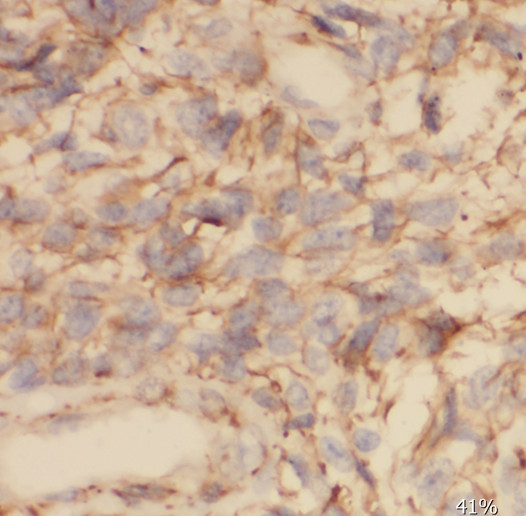

| 验证图片 | Immunohistochemistry of paraffin-embedded human gliomas using FNab07658(SCRN2 antibody) at dilution of 1:50 BxPC-3 cells were subjected to SDS PAGE followed by western blot with FNab07658(SCRN2 antibody) at dilution of 1:400 |